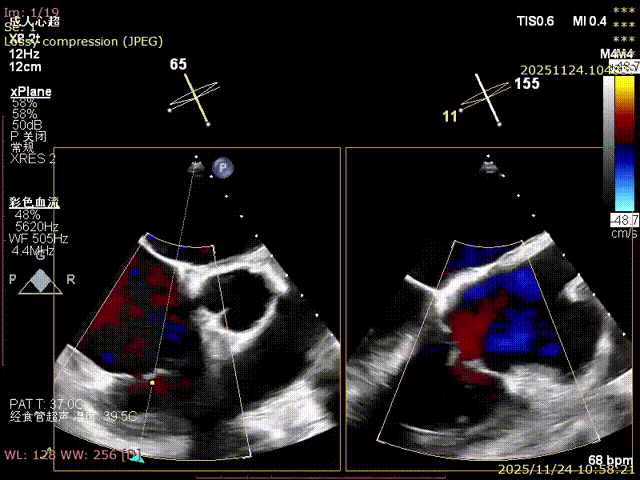

During the procedure, close collaboration was maintained with Dr. Yang Yan (anesthesiologist, Department of Anesthesiology) and Dr. Niu Ming (echocardiography specialist, team of Director Zhai Hong, Department of Cardiac Ultrasound). Guided by transesophageal echocardiography and assisted by DSA imaging, the tricuspid annular structure and regurgitation jet direction were precisely assessed. Ultimately, two 12T K-Clip® devices were successfully implanted. Immediate postoperative echocardiographic evaluation showed a significant reduction in tricuspid regurgitation from 4+ preoperatively to 1+, with a marked decrease in annular area. The surgical outcome was satisfactory.

Echocardiographic: Severe tricuspid regurgitation (grade 4+), with the regurgitant jet mainly located at the posteroseptal and central regions. No significant dilatation of the tricuspid annulus is observed. Mild myxomatous degeneration of the tricuspid leaflets is present, showing Barlow-like morphology, with leaflet prolapse of 3.7 mm in height.

Evaluating the effect.

Preoperative Regurgitation: 4+

Annulus Area: 11.3 cm²

Postoperative Regurgitation: 1+

Annulus Area: 4.9 cm²